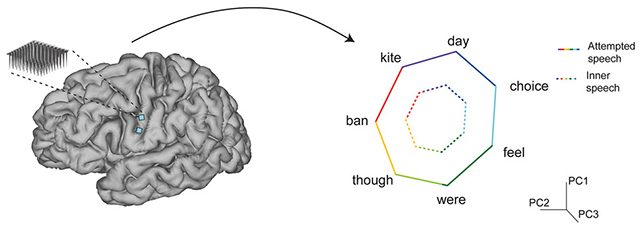

پیشرفتهای اخیر در علوم عصبی و مهندسی مغز، زمینهساز توسعه فناوریهای نوینی شده که ممکن است آینده ارتباط انسان و ماشین را متحول کنند. یکی از پیشگامترین دستاوردها در این حوزه، نخستین دستگاه مغزی برای خواندن گفتار درونی است. این دستگاه قادر است سیگنالهای مغزی مرتبط با افکار گفتاری را شناسایی و ترجمه کند و امکان ارتباط بدون گفتار یا نوشتار را فراهم نماید.

گفتار درونی یا inner speech، فرآیندی است که در آن فرد بدون بیان صدا، افکار خود را به شکل کلامی در ذهنش مرور میکند. این نوع گفتار در مغز فعالیتهای مشابه گفتار واقعی ایجاد میکند، اما سیگنالها به عضلات صوتی منتقل نمیشوند.

فعالیت در مناطق Broca و Wernicke مغز مرتبط با گفتار درونی است.

امواج مغزی ناشی از این فعالیتها قابل شناسایی با دستگاههای پیشرفته هستند.

این دستگاه با استفاده از الکترودهای حساس و الگوریتمهای هوش مصنوعی سیگنالهای مغزی مرتبط با افکار گفتاری را ثبت میکند. مراحل اصلی عملکرد شامل:

ثبت سیگنالهای عصبی: از طریق الکترودهای غیرتهاجمی یا نیمهتهاجمی، فعالیت مغز ضبط میشود.

پردازش دادهها: سیگنالهای پیچیده مغزی به الگوریتمهای یادگیری ماشین داده میشوند.

ترجمه گفتار درونی: مدل هوش مصنوعی الگوهای مغزی را به کلمات یا جملات قابل خواندن تبدیل میکند.